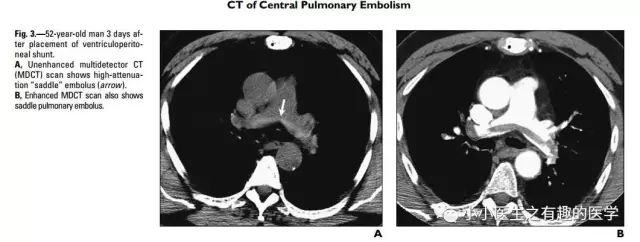

上面图片的英文原版

↓↓↓

病例二

作者单位:Department of Radiology, University of Washington MedicalCenter, University of Washington School of Medicine(华盛顿医科大学)。

翠花上菜,学者上图。

发现嫌疑犯,立即逮捕。

增强CT对比,一目了然。